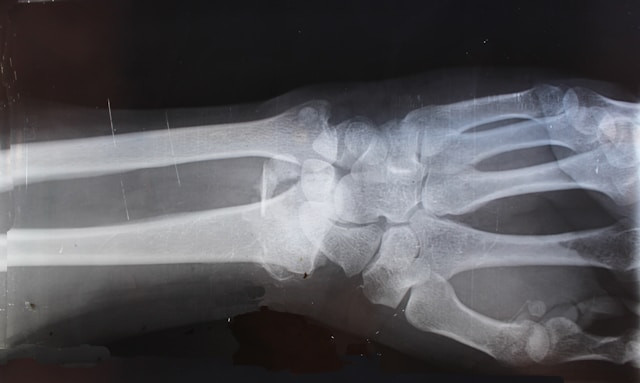

A distal radius fracture, often called a wrist fracture, occurs when the larger forearm bone breaks near the wrist. This injury is commonly caused by falls onto an outstretched hand and may involve joint displacement or ligament damage.

We use state-of-the-art tools including digital X-rays, ultrasound, and CT scans when needed to clearly visualize the fracture pattern. This allows us to determine the best treatment plan and identify any joint involvement or associated injuries.